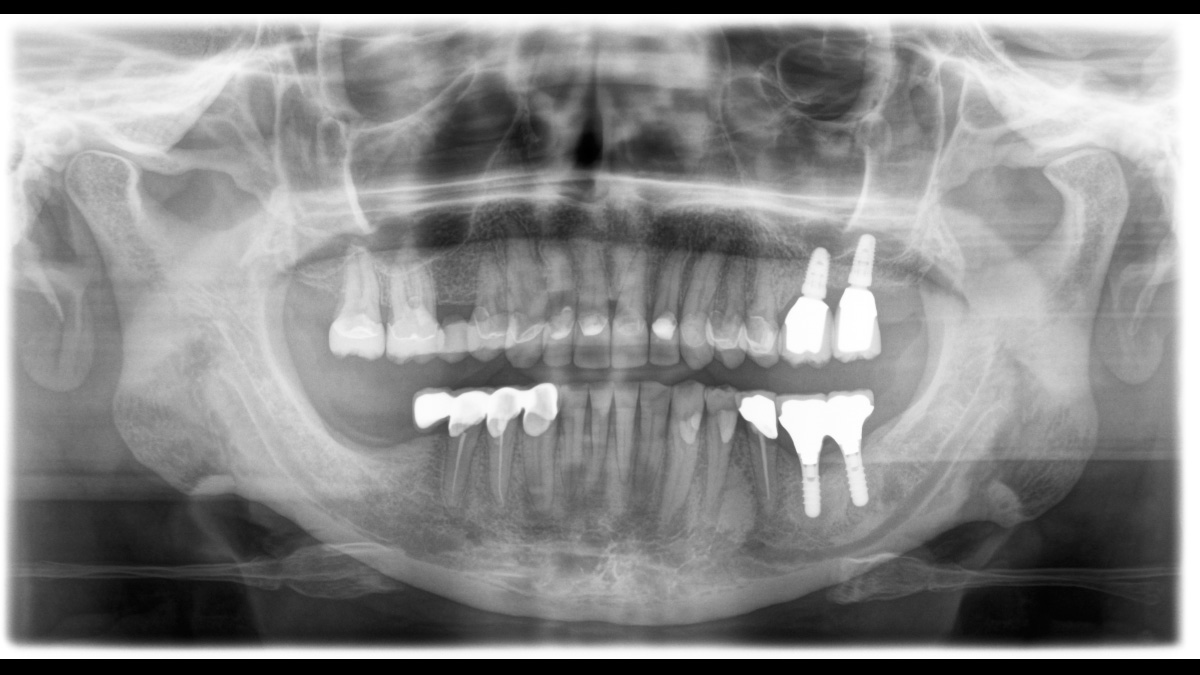

The high-quality 2D/3D X-ray device with a comprehensive range of services for every practice. Whether as a pure 2D device or including a 3D module – the Orthophos S is a reliable partner and optimized for everyday tasks. Its CsI Plus sensor with autofocus function ensures clear images, even in anatomically difficult cases. The automatic patient positioning together with the patented occlusal bite block enables an easy and timesaving patient positioning. For use in orthodontics, the Orthophos S is also available with an optional ceph arm. And because future-proofing is important to Dentsply Sirona, the cephalometric arm can be retrofitted at any time.

With the 3D Intelligent Low Dose mode, you get 3D images in the dose range of a 2D X-ray. In HD mode (up to 1,400) individual images are captured during a single rotation and converted into a 3D volume with up to 80 μm for low-noise images in high resolution.

The right focus is crucial for excellent panoramic radiographs. With the autofocus function you will automatically receive an image with the best possible sharpness in focus. The Orthophos S creates several thousand individual images in one revolution and automatically recognizes the areas in which the jaw is optimally positioned. A sharp panoramic image is created from the individual projections – without any manual intermediate steps.